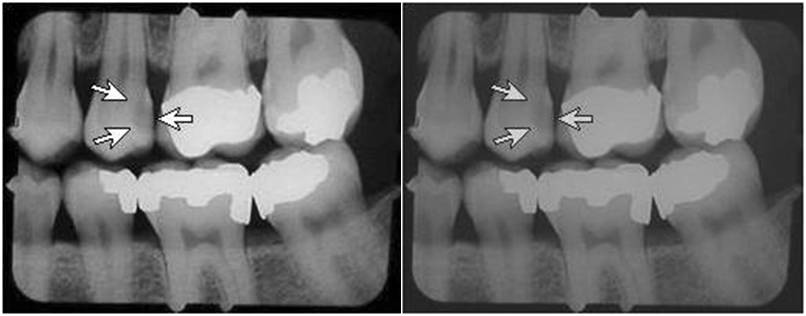

Twelve Contrast is a measure of the differences in the film densities. In other words, this is a measure of whether the film is black and white, or gray all over. Image sharpness is affected by the kVp and beam filtration (high kVp or high beam filtration reduces the film contrast), processing conditions (low developer temperature, short development time, or exhausted or not properly replenished developer) or contaminated developer solution will reduce contrast. In addition, contrast varies with the type and age of film used.

Low contrast will make small details difficult to see and will also make it difficult to visualize larger structures in the image which are similar in density to the surrounding tissue, e.g., a tumor in soft tissue.

Contrast is the optical density difference between two areas on the x-ray film that have received known exposures.

Normal on left, low contrast on right.